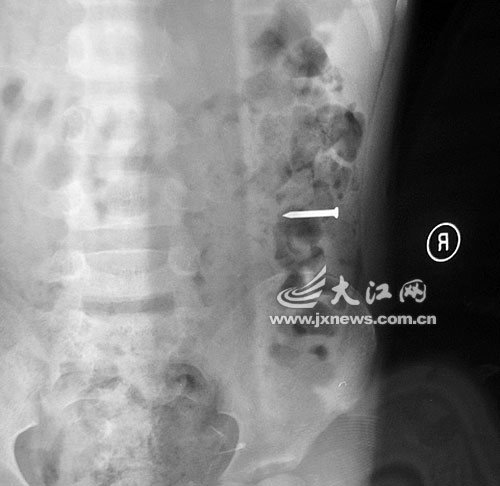

江西留守儿童吞硬币留父母:勇勇误吞铁钉后的X光片

事发当晚,勇勇的奶奶雇了一辆面包车,连夜将勇勇送往都昌县人民医院救治。当晚,医院经过拍片发现,2.5厘米的铁钉滑到孩子的胃部。